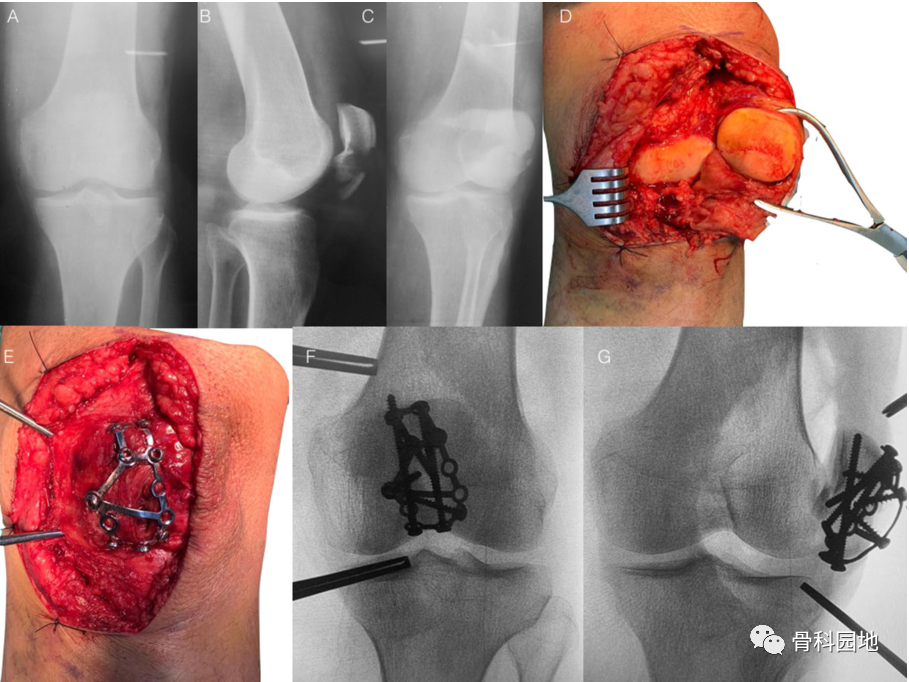

四、股骨内侧髁骨折

股骨内侧髁粉碎性骨折,应用跟骨板复位固定。主要指征是严重粉碎骨折。但如果存在剪切力,单个跟骨板可能不足以 支撑该力。

五、髌骨骨折

四颗 3.5mm 皮质螺钉用作拉力螺钉,两颗从上到下,两颗从下到上多个方向固定